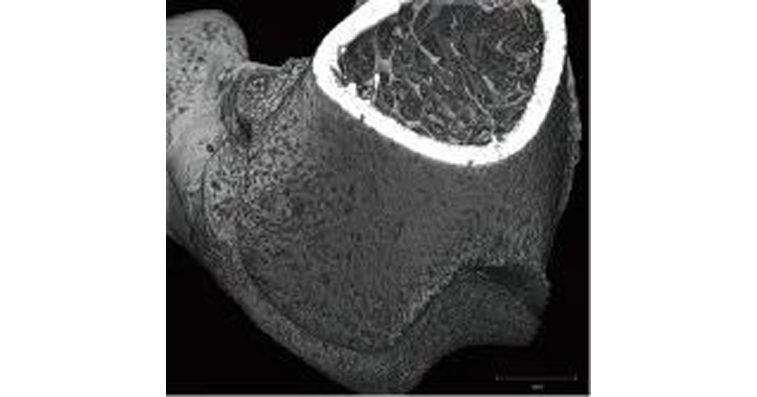

图8 小鼠股骨的三维图像

使用X射线CT获取图像,不仅可以进行横断面和三维观察,而且可以单独提取感兴趣区域进行观察,并测量骨的厚度。

图9 小鼠股骨三维图像